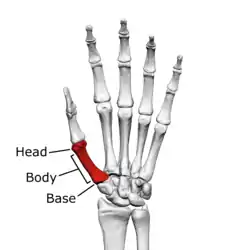

![]() First metacarpal of the left hand (shown in red). Palmar view. | |

The first metacarpal bone or the metacarpal bone of the thumb is the first bone proximal to the thumb. It is connected to the trapezium of the carpus at the first carpometacarpal joint and to the proximal thumb phalanx at the first metacarpophalangeal joint.

Characteristics

The first metacarpal bone is short and thick with a shaft thicker and broader than those of the other metacarpal bones. Its narrow shaft connects its widened base and rounded head; the former consisting of a thick cortical bone surrounding the open medullary canal; the latter two consisting of cancellous bone surrounded by a thin cortical shell. [1]

Head

The head is less rounded and less spherical than those of the other metacarpals, making it better suited for a hinge-like articulation.

The distal articular surface is quadrilateral, wide, and flat; thicker and broader transversely and extends much further palmarly than dorsally. On the palmar aspect of the articular surface there is a pair of eminences or tubercles which articulate with the radial and ulnar sesamoid bones of the thumb metacarpophalangeal joint; the lateral eminence is larger than the medial.

Body/Shaft

The body or shaft is thick and broad — averaging 6 to 11 millimetres (0.24 to 0.43 in). On its dorsal side, the shaft is flat and wide, while the anteroposterior side is less pronounced; usually resulting in an oval-triangular cross-section.

The dorsal surface of the shaft is weakly convex longitudinally, while its palmar, radial, and ulnar surfaces tend to be concave. The palmar and medial surface exhibits a blunt ridge which separates a larger lateral part – the insertion of the opponens pollicis muscle – and a smaller medial part – the origin of the lateral head of the first dorsal interosseous muscle.

Base

The base is significantly different from the bases of the other metacarpals. It is trumpet-shaped and ends in a saddle-shaped articular surface matching that of the trapezial articular surface. The configuration of the thumb carpometacarpal joint plays an important role in the mechanism of opposition. The articular surface is delimited by a thick, crest-like ridge extending around its circumference.

On the palmar and lateral side of the base is the insertion of the tendon of the abductor pollicis longus muscle, usually featuring a small tubercle. The origin of the first dorsal interosseous muscle is on the ulnar aspect of the base, and can sometimes extend onto the shaft. In contrast to the other metacarpals, the first metacarpal has no articular facets on the sides of its base (for intermetacarpal articulations) because it articulates exclusively with the trapezium.